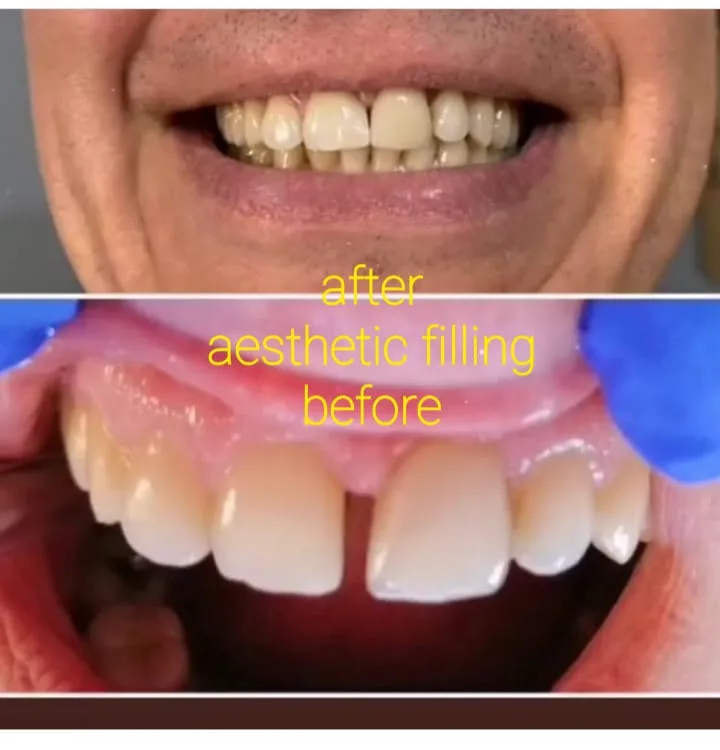

Odontologia estética: branqueamento e restauração